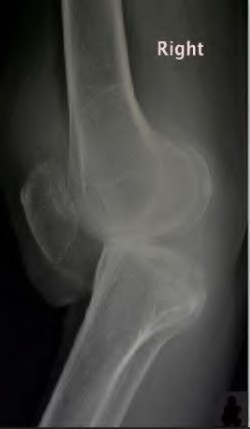

A 65-year-old woman with painful knee arthritis and the deformity seen in Figure A, is scheduled to undergo a total knee arthroplasty. All the following are risk factors for a post-operative peroneal palsy EXCEPT:

Figure A demonstrates and AP radiograph of the knee showing end-stage arthritis with severe lateral compartment narrowing.